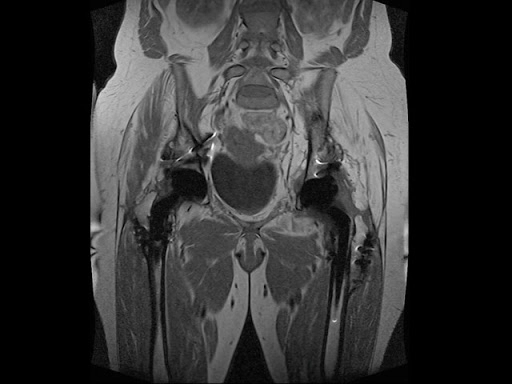

МРТ малого таза с контрастом

Одним из наиболее информативных и при этом абсолютно безвредных диагностических исследований является МРТ органов малого таза с контрастированием.

МРТ с контрастированием – высокоточный метод диагностики, при котором вводится специальный препарат для улучшения визуализации тканей с целью точного определения размеров, границ и характера патологий – опухолей, воспалений и сосудистых аномалий.

Для проведения МРТ таза с контрастом используется томограф последнего поколения MAGNETOM Skyra с мощностью магнитного поля 3 Тл. Диаметр тоннеля установки составляет 70 см, а грузоподъемность стола – 250 кг, благодаря чему отсутствуют ограничения для пациентов с ожирением. Технология параллельной визуализации позволяет получать изображения с максимально высокой четкостью и создавать на компьютере объемную модель внутренних органов малого таза.